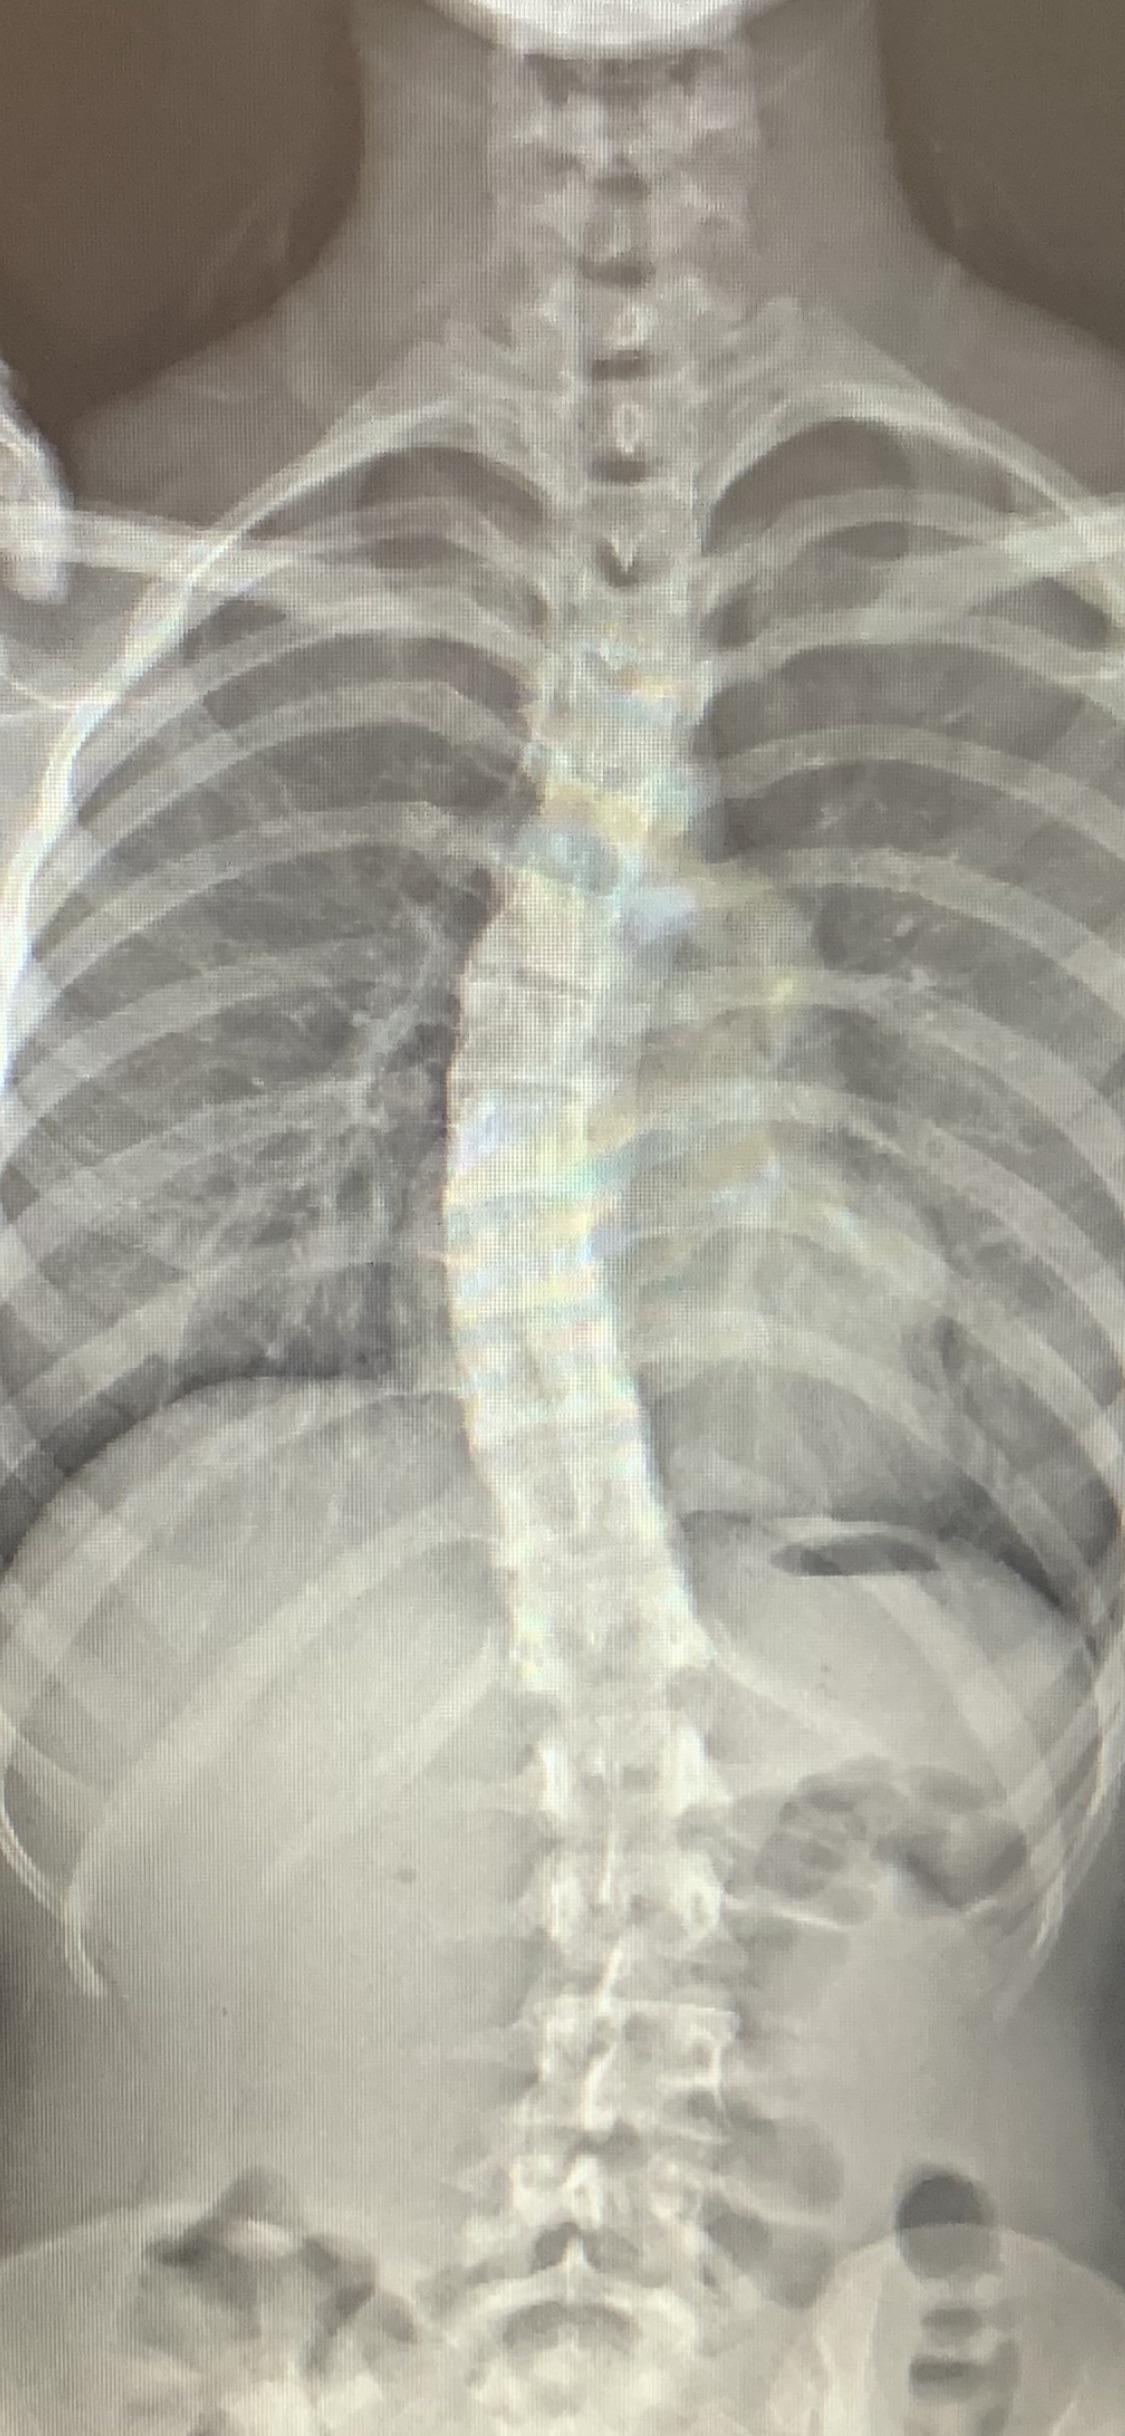

Color XRay of a severe Scoliosis. This severe type of Scoliosis often Ribs Hurt Scoliosis You may feel thoracic scoliosis pain in your back and shoulders. As scoliosis worsens, it can cause more noticeable changes — including uneven hips and shoulders, prominent ribs, and a shift of the waist and trunk. When an unnatural thoracic curve exposes the spine and its surroundings to uneven pressure, the spine can pull on. Particularly common with curvatures along. Ribs Hurt Scoliosis.